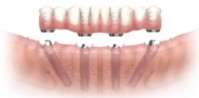

それでは、具体的に全体的な場合を例にとってみましょう。

例えば、何本かの歯が残っていてこれを柱にしてブリッジがかかっていて、

すべての根っ子がダメで抜かなければならないとします。

という差があり「従来の方法」の「とりあえず、取りはずしの総入れ歯」の時期が無くなるのです。